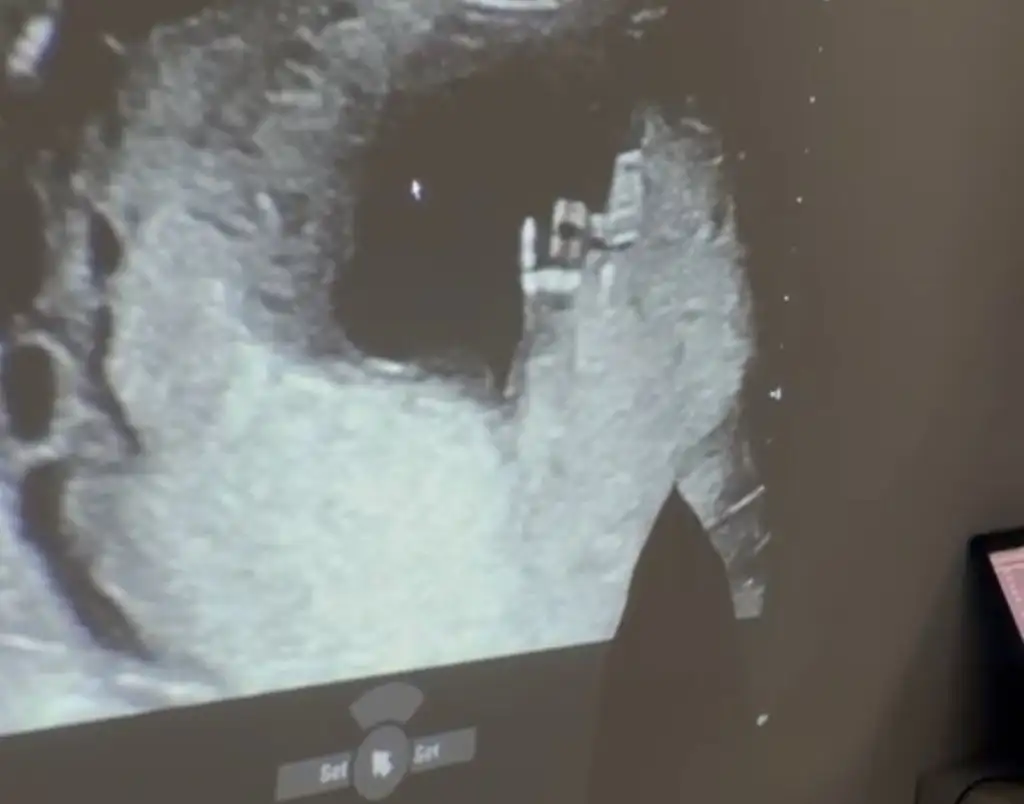

Selammm 😊😊😊 bebişim bugün el salladı bize 💕🙏🐣😀

• IMG_4965.webp